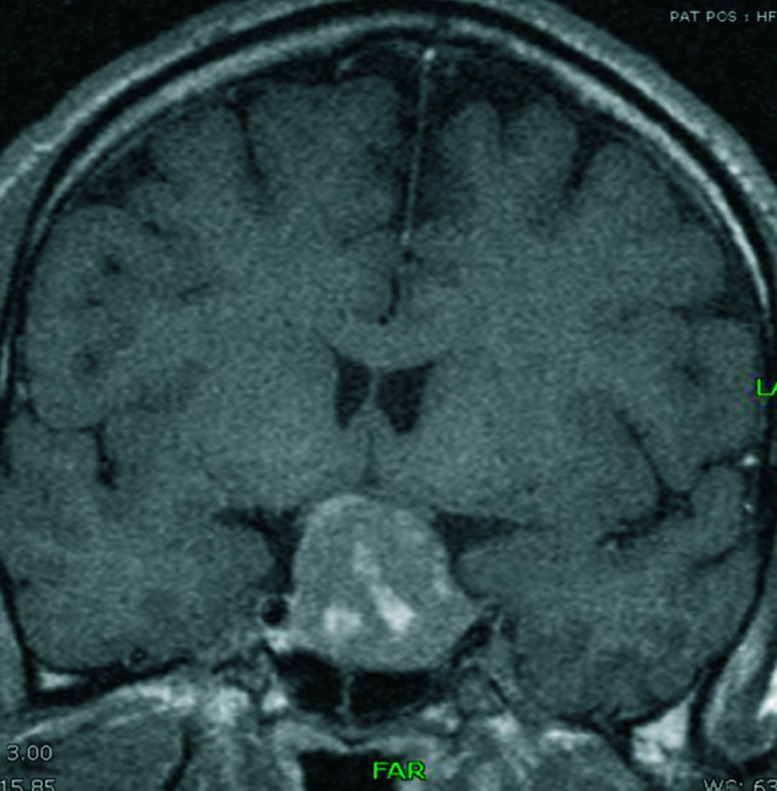

Unlabelled: A 53-year-old male presented with recurrent calcium oxalate kidney stones as a first sign of underlying acromegaly, which vanished when his acromegaly was controlled. The exact mechanism behind hypercalciuria and urolithiasis in acromegaly is not yet clear. By discussing this case, a short overview of the pathophysiology of hypercalciuria in acromegaly and practical insights are given.

Learning points: Hypercalciuria is a common finding in acromegaly.There are only few reports describing hypercalciuric kidney stones in acromegaly.We assume that in acromegaly there is a primary role of IGF1-mediated, PTH-independent increase in calcitriol synthesis resulting in hypercalciuric kidney stones.